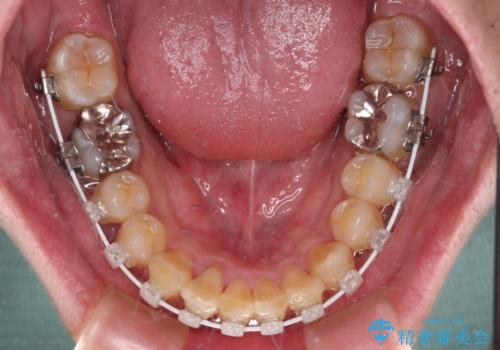

- 審美装置

- 深い咬み合わせによる食いしばりで、顎関節や頭が痛むことがあるとのことで来院された患者様です。

歯ぎしりができないくらい強い食いしばりの咬合状態であったため、奥歯の歯軸を起き上がらせることで咬合を挙上させ、歯ぎしりができるようにしていくこととしました。

インビザラインでの矯正治療も可能でしたが、自己管理の煩わしさを嫌ってワイヤー装置による矯正治療を行うこととしました。